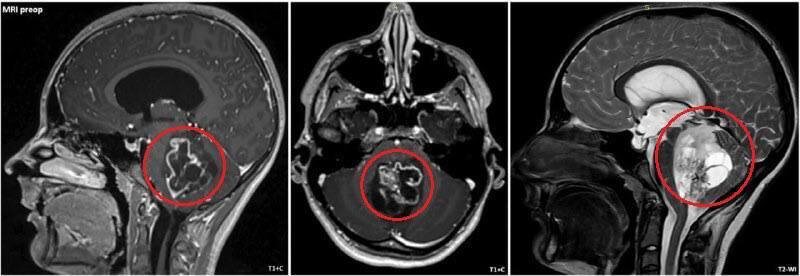

Π’ ДСтском клиничСском Ρ†Π΅Π½Ρ‚Ρ€Π΅ ΠΈΠΌ. Рошаля Π²Ρ€Π°Ρ‡ΠΈ спасли подростка, ΠΏΠΎΡΡ‚ΡƒΠΏΠΈΠ²ΡˆΠ΅Π³ΠΎ с постоянной Ρ‚ΠΎΡˆΠ½ΠΎΡ‚ΠΎΠΉ ΠΈ Ρ€Π²ΠΎΡ‚ΠΎΠΉ, ΠΊΠΎΡ‚ΠΎΡ€Ρ‹Π΅ Π½Π΅ поддавались Π»Π΅Ρ‡Π΅Π½ΠΈΡŽ.

πŸ“ ОбслСдованиС ΠΏΠΎΠΊΠ°Π·Π°Π»ΠΎ ΠΎΠ±ΡŠΡ‘ΠΌΠ½ΠΎΠ΅ ΠΎΠ±Ρ€Π°Π·ΠΎΠ²Π°Π½ΠΈΠ΅ Π² Π·Π°Π΄Π½Π΅ΠΉ Ρ‡Π΅Ρ€Π΅ΠΏΠ½ΠΎΠΉ ямкС β€” ΠΎΠΏΡƒΡ…ΠΎΠ»ΡŒ Ρ€Π°Π·ΠΌΠ΅Ρ€ΠΎΠΌ ΠΎΠΊΠΎΠ»ΠΎ 5 см. Она Π½Π°Ρ…ΠΎΠ΄ΠΈΠ»Π°ΡΡŒ Π² Π·ΠΎΠ½Π΅, ΠΎΡ‚Π²Π΅Ρ‡Π°ΡŽΡ‰Π΅ΠΉ Π·Π° ΠΆΠΈΠ·Π½Π΅Π½Π½ΠΎ Π²Π°ΠΆΠ½Ρ‹Π΅ Ρ„ΡƒΠ½ΠΊΡ†ΠΈΠΈ, ΠΈ прСдставляла ΠΏΡ€ΡΠΌΡƒΡŽ ΡƒΠ³Ρ€ΠΎΠ·Ρƒ ΠΆΠΈΠ·Π½ΠΈ.

πŸ‘¨β€βš•οΈ Π₯ΠΈΡ€ΡƒΡ€Π³ΠΈ ΠΏΡ€ΠΎΠ²Π΅Π»ΠΈ ΡΠ»ΠΎΠΆΠ½Π΅ΠΉΡˆΡƒΡŽ ΠΎΠΏΠ΅Ρ€Π°Ρ†ΠΈΡŽ с ΠΏΡ€ΠΈΠΌΠ΅Π½Π΅Π½ΠΈΠ΅ΠΌ ΡƒΠ»ΡŒΡ‚Ρ€Π°Π·Π²ΡƒΠΊΠΎΠ²ΠΎΠ³ΠΎ аспиратора, Π°ΠΊΠΊΡƒΡ€Π°Ρ‚Π½ΠΎ ΡƒΠ΄Π°Π»ΠΈΠ² Π½ΠΎΠ²ΠΎΠΎΠ±Ρ€Π°Π·ΠΎΠ²Π°Π½ΠΈΠ΅, Π½Π΅ ΠΏΠΎΠ²Ρ€Π΅Π΄ΠΈΠ² ΠΏΡ€ΠΈ этом критичСскиС структуры ΠΌΠΎΠ·Π³Π°.